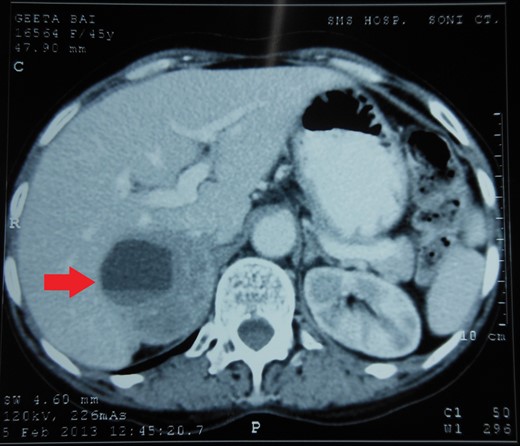

Routine laboratory tests were unremarkable. Ultrasound of the abdomen showed a 5 × 5 cm solid-cystic mass overlying the right kidney. CECT abdomen confirmed the presence of a right suprarenal tumour measuring 6 × 5 × 5 cm with solid-cystic components and fluid levels suggestive of intratumoural haemorrhage. Magnetic resonance imaging (MRI) of abdomen suggested an space occupying lesion in the right adrenal gland with multiple cystic spaces of variable sizes suggestive of pheochromocytoma. Fat planes to the adjacent structures were preserved with no evidence of metastases (Figs 1–4).

CECT abdomen showing an inhomogeneously dense right suprarenal mass (TRANSVERSE SECTION).